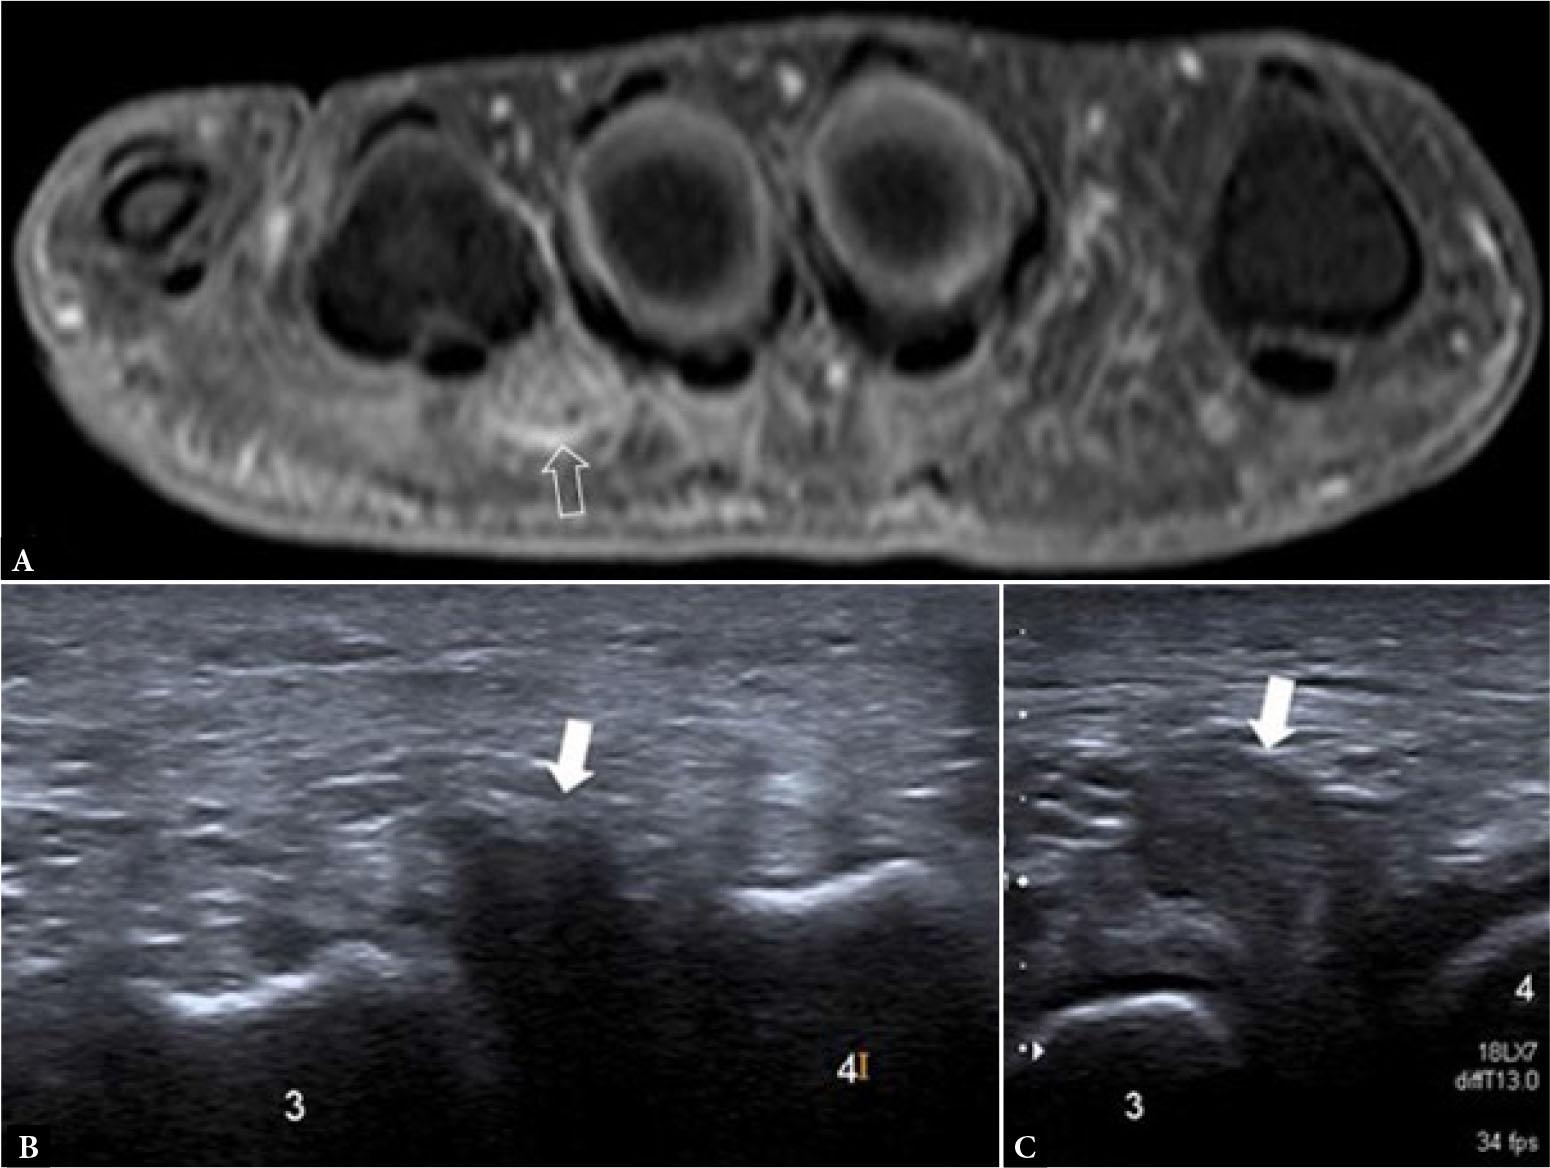

Morton’s neuroma is mostly seen in middle-aged women, and is possibly related to mechanical loading from high-heeled shoes. Patients typically have intermetatarsal head pain or numbness radiating to the adjacent toes. US, which can be performed from either the dorsal or plantar side, allows close clinical correlation and dynamic assessment(13). Pressure with the thumb from the dorsal aspect of the forefoot as well as the squeeze test (Mulder’s maneuver) help move the hypoechoic neuroma towards the plantar placed transducer(13) (Fig. 20). This displacement of the neuroma may be accompanied by a palpable, or even audible, click. On longitudinal US, Morton’s neuroma is seen as a normal fibrillar echogenic common interdigital nerve coursing into a focal heterogeneous hypoechoic mass about 14 mm in length (range, 9.0–24.0 mm) containing a more central echogenic area, about 7.5 mm in length(21). The central echogenic area more closely approximates the size of the actual neuroma histologically with the surrounding hypoechoic area representing scar tissue(21). On histology, the resected neuroma will comprise a “neuroma-bursal complex” consisting of the thickened degenerated nerve, fibrotic perineurium, tangled vessels, and scarred/ thickened bursa(21). A neuroma >5 mm in transverse dimension is more likely to be symptomatic(13).

Fig. 20.

Morton’s neuroma in two different patients. A. Coronal gadolinium-enhanced T1W TSE fat-suppressed image shows inhomogeneous enhancement of a rounded mass (open arrow) on the plantar aspect of the third webspace, consistent with a Morton’s neuroma. B. On greyscale transverse US image of the third webspace, a hypoechoic mass is seen (arrow), which C. becomes more prominent using the squeeze test

On MRI, Morton’s neuroma is seen as a rounded to spindle-shaped T1-intermediate signal, T2-hypointense mass in the inferior intermetatarsal space, either with or without contrast enhancement. Visible continuity with the plantar digital nerve (‘rat’s tail sign’) also improves diagnostic confidence. In contrast, intermetatarsal bursitis is more cyst-like, with rim enhancement in the superior intermetatarsal space (Fig. 17)(22). Both US and MRI have comparable high sensitivity for diagnosing Morton’s neuroma, with US being more cost-effective(23).